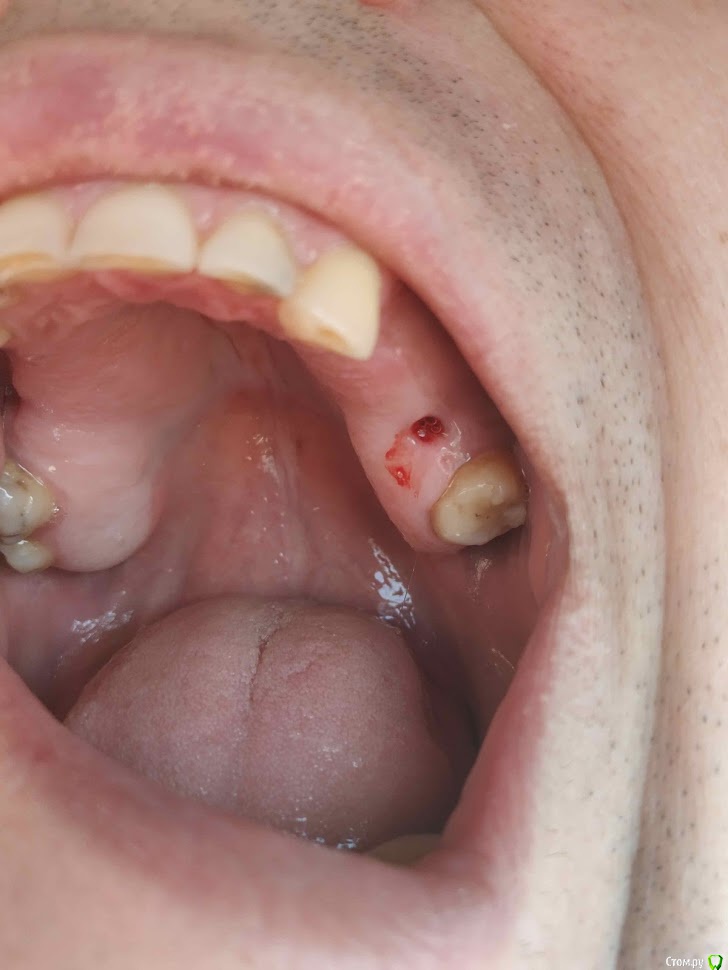

Валдемар Опубликовано 29 августа, 2019 Поделиться Опубликовано 29 августа, 2019 Добрый день,Уже был здесь, но прошлые явки и пароли забыл.12.04 операция 4 импланта20.04 вылез первый15.05 вылез второй26.08 удален 3ий28.08 удален 4ыйПотрачено 100тр, время и нервы. Возвращено 7200 за 2 импланта, за 2 которые удаляли деньги не вернули, так как не было показаний. А то что голова болит, переносица, лоб - ет не от этого. Удалил и всё прошло, кстати.Вопрос:1). Справа десны (кости) реально меньше чет слева. Что с этим делать. Как сделать чтобы кости хоть немного прибавилось? Без имплантации, просто кость с десной нарастить.2) 100% неприживаемости - ето как? Диабет, спид, гепатит по диспансаризации сдавал - отрицательно. Какие мои действия теперь? по новой имплантироваться и если опять не приживется, опять по новой? Ссылка на комментарий

Валдемар Опубликовано 30 августа, 2019 Автор Поделиться Опубликовано 30 августа, 2019 Два недоконца или как тпм вкрутили и организм смог их сам выдавить, а два пришлось доктора помощь просить, организм не справлялся Ссылка на комментарий

Валдемар Опубликовано 31 августа, 2019 Автор Поделиться Опубликовано 31 августа, 2019 Я снимок после удаления не делал, но у меня реально справа десна тоньще раза в два. Там воспаление месяца два шло. В имплантацию больше не верю, вернее, боюсь. Боюсь нового стресса для организма. Верил в современную медицину, российскую, смотрел на людей с коленками кривыми, тазобедренными суставами проблемными, говорил че вы ждете, щас раз и коленку и тазобед сустав меняют и как новенький, а теперь понимаю, фиг там. Китайское что рибудь поставят, или руки у дохтора не оттудава, и всё, можно на костылях оставшуюся жизнь бегать...Потому люди до последнего и тянут. Ссылка на комментарий